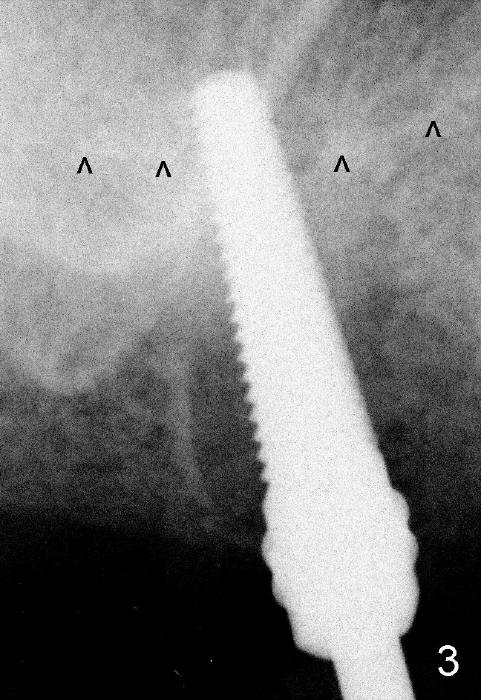

The upper right 1st molar fractures, the lingual portion mobile (Fig.1). There are deep pockets mesiolingually and distolingually. Fig.2 is preop PA, showing mesial bone resorption (*). The 84-year-old lady agrees extraction and immediate implant. Extraction is difficult due to not only root fracture but also hemorrhage. Following debridement of granulation tissue, the 3 sockets are packed with gauze for hemostasis. Even so, there is oozing from the bone. The septum can not be seen clearly. Its position is determined by an explorer. Osteotomes have to be used for osteotomy in the septum, followed by taps. The first intraop PA shows that 5x20 mm tap penetrates the sinus floor (Fig.3 ^). The osteotomy is further enlarged until 7x17 mm tap with stability (Fig.4). So far there has been no sign of sinus membrane perforation. Mixture of freeze dry mineralized bone and Osteogen is placed in the socket and pushed to the buccal and lingual walls as well as into sinus using a 4 mm flat end osteotome. A 7x17 mm implant is initially difficult to be inserted possibly due to blockage by bone graft. The osteotomy have to be recreated by a series of osteotomes and taps before placement of the 7x17 mm implant. It appears that the apical threads have been engaged into the sinus floor for primary stability (Fig.5). The insertion torque is 40 Ncm. According to our experience (1,2), this is not enough; finally the torque is increased to 60 Ncm by turning the implant more apically. The large implant obliterates the socket mesiodistally; the buccal and lingual gaps are filled with bone graft, followed by a collagen membrane (Fig.6 *) and suture. In order to protect the membrane, a short abutment is placed (A) and perio dressing (Fig.7*) is placed without occlusal interference. The abutment is removed 1 month postop, as the perio dressing has been dislodged. The patient returns for restoration 8 month postop. Bone regeneration occurs apparently in the coronal aspect of the implant (Fig.8), especially mesially (*, as compared to Fig.5). The gingiva-level implant is slightly subgingival mesially (Fig.9 M), probably due to high placement (compare to Fig.6). There is no bone resorption 6 months post crown (Fig.10 C) cementation.